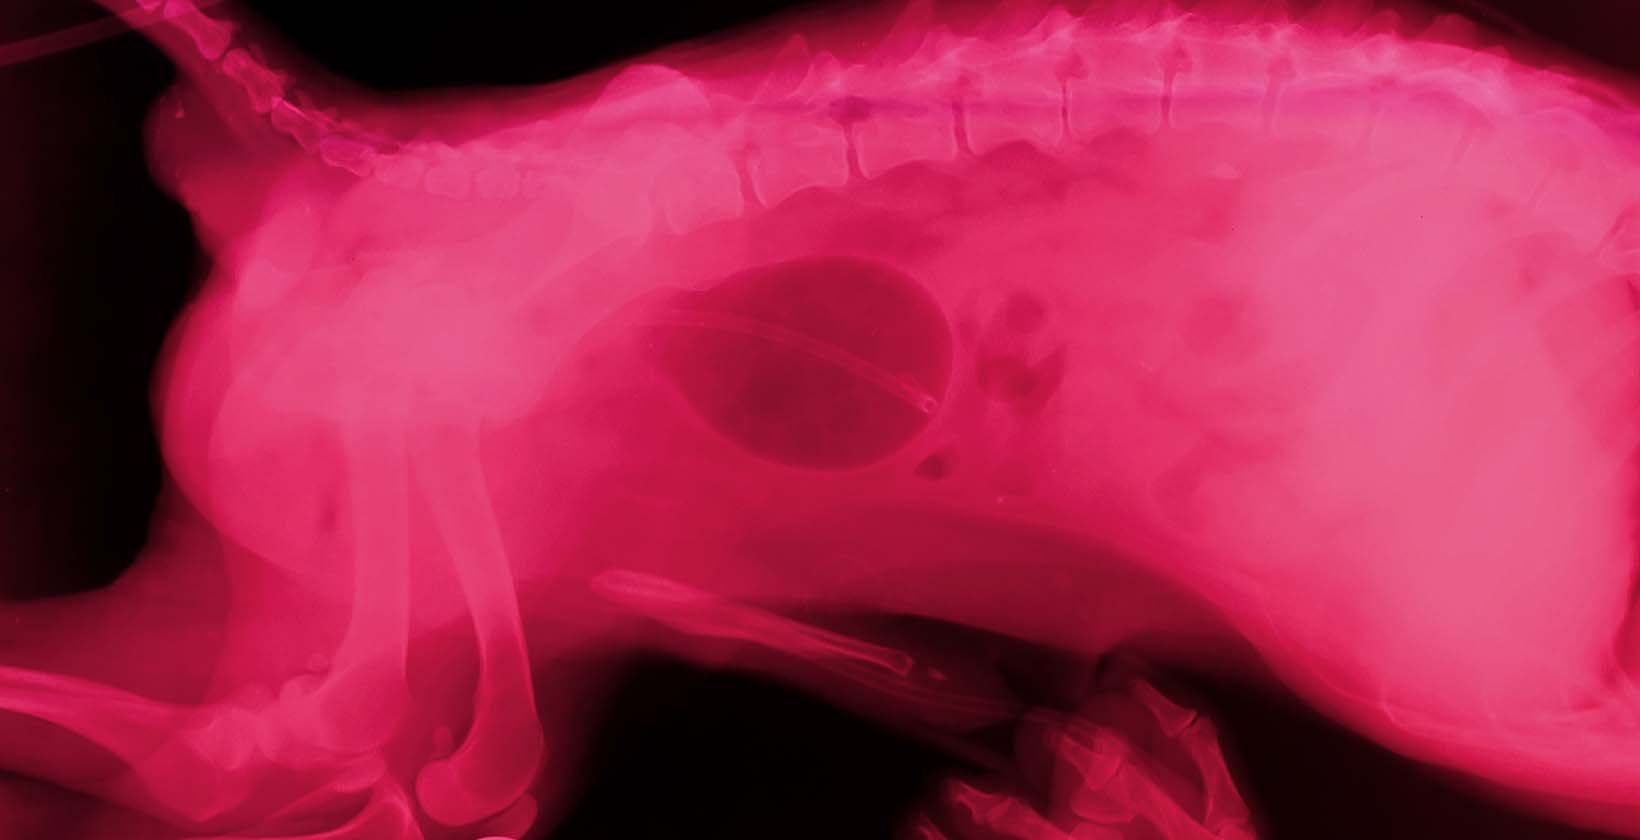

IVDD in dogs, or intervertebral disc disease, is a spinal condition in which an intervertebral disc herniates (pops out of its place) and exerts pressure on the spinal cord and nerves.

The dog’s spine is made of small bones called vertebrae separated by cushions known as discs. The discs consist of gelatinous centers and thick outer shells. Dog IVDD occurs when discs slip, burst, or degenerate.